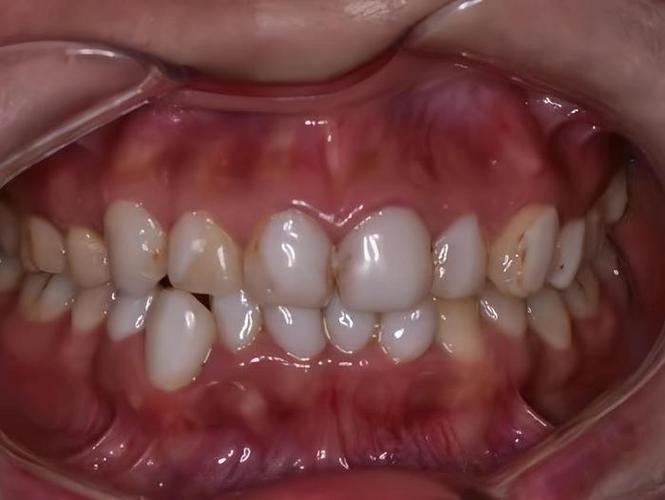

正畸失败最直接的后果是牙齿排列异常未纠正或出现新的问题,常见表现包括:牙齿反弹移位(如原本内收的门牙再次外凸、牙缝重新出现)、咬合干扰(后牙咬合时某颗牙齿过早接触,导致咀嚼受力不均)、深覆颌或深覆盖复发(上下牙垂直或水平覆盖关系未稳定)、开颌(上下牙无法正常咬合,出现缝隙)等,此类问题多因矫正方案中未充分考虑牙齿稳定性(如未解决骨性问题、支抗设计不足)、保持器佩戴时间不够或终身维护中断,导致牙齿在肌肉力量或咬合压力下逐渐移回原位。

牙齿移动过程中,若施力过大、移动速度过快,或患者口腔卫生维护不当,易引发牙周组织损伤,表现为牙龈萎缩(牙根暴露,牙齿敏感)、牙槽骨吸收(X光片可见牙槽骨高度降低)、牙周袋形成(牙龈与牙齿间缝隙加深,易藏食物残渣),严重时,牙齿因失去骨支持而松动,甚至脱落,正畸装置(如托槽、弓丝)若长期刺激牙龈,可能导致牙龈增生或炎症,进一步破坏牙周健康。

正畸移动牙齿过程中,牙根尖端可能出现吸收(牙根长度变短),严重时牙根呈“钝圆形”,影响牙齿稳定性,牙根吸收多与施力过大、移动速度过快、个体易感性(如部分患者牙根天生较细)有关,若矫正装置安装不当(如托槽粘贴位置错误),可能磨损牙釉质,甚至导致牙齿折裂。